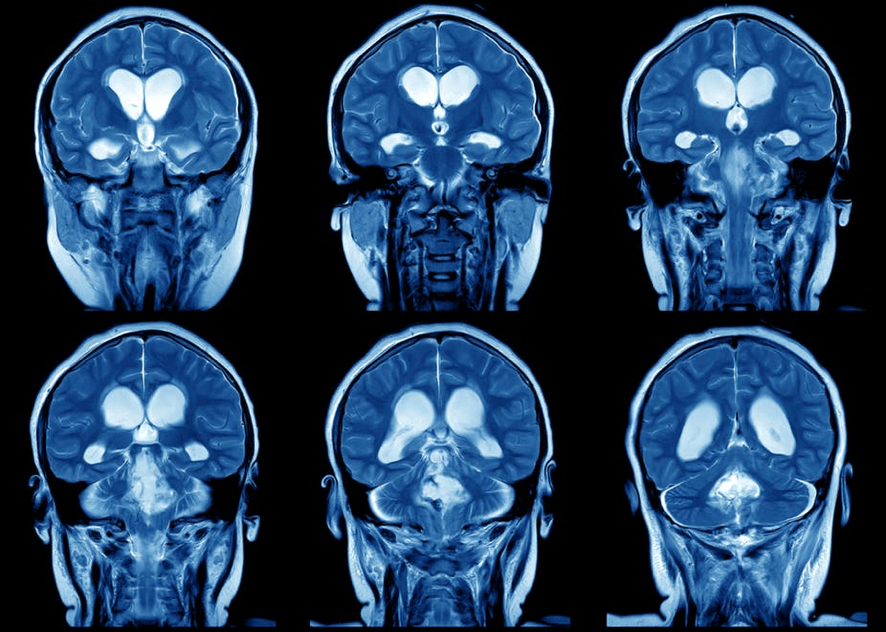

Mamíferos sem corpus callosum e a evolução das conexões entre os dois lados do cérebro

Os dois lados do cérebro são anatomicamente idênticos, mas não são independentes. Neurônios projetam seus axônios de um lado ao outro, integrando a atividade neuronal que ocorre em cada lado. O cruzamento ocorre em regiões específicas da linha media do cérebro chamadas de comissuras. Em humanos, a principal comissura é chamada corpus callosum e conecta os hemisférios do neocórtex, a grande região anterior do cérebro de mamíferos.

Os neurônios que cruzam o corpus callosum conectam áreas similares nos lados direito e esquerdo do neocórtex. Voltando ao exemplo da mão, a área do neocórtex que controla a mão esquerda está conectada à que controla a mão direita (conexão homotípica) e o braço direito (conexão heterotípica), permitindo a coordenação da atividade das duas mãos. Pessoas que nascem sem corpus callosum, entre outros problemas, apresentam dificuldades para coordenar atividades motoras e visuais dos dois lados do corpo. Porém, os problemas de integração dos hemisférios são bem mais pronunciados em pessoas que nascem com corpus callosum e o perdem por uma lesão.

Todos os mamíferos têm neocórtex, mas nem todos têm corpus callosum: os marsupiais (mamíferos que terminam o desenvolvimento embrionário fora do útero, como os cangurus) e monotremas (mamíferos que nascem de um ovo, como o ornitorrinco), não têm corpus callosum. Como eles integram então a atividades dos dois lados do cérebro?

Para poder estudar um animal raro como o ornitorrinco, eles realizaram ressonâncias magnéticas em dois indivíduos depositados em uma coleção zoológica (sim, os museus servem para investigação!) e reconstruíram digitalmente as projeções neuronais no neocórtex (vejam nos vídeos abaixo). Repetiram o mesmo experimento em um pequeno marsupial australiano chamado Dunnart (Sminthopsis crassicaudata). O trabalho mostra que neurônios que cruzam de um lado ao outro pela região ventral do cérebro (chamada de comissura anterior, presente em todos os mamíferos) conectam os neocórtex dos dois hemisférios em marsupiais e monotremas.